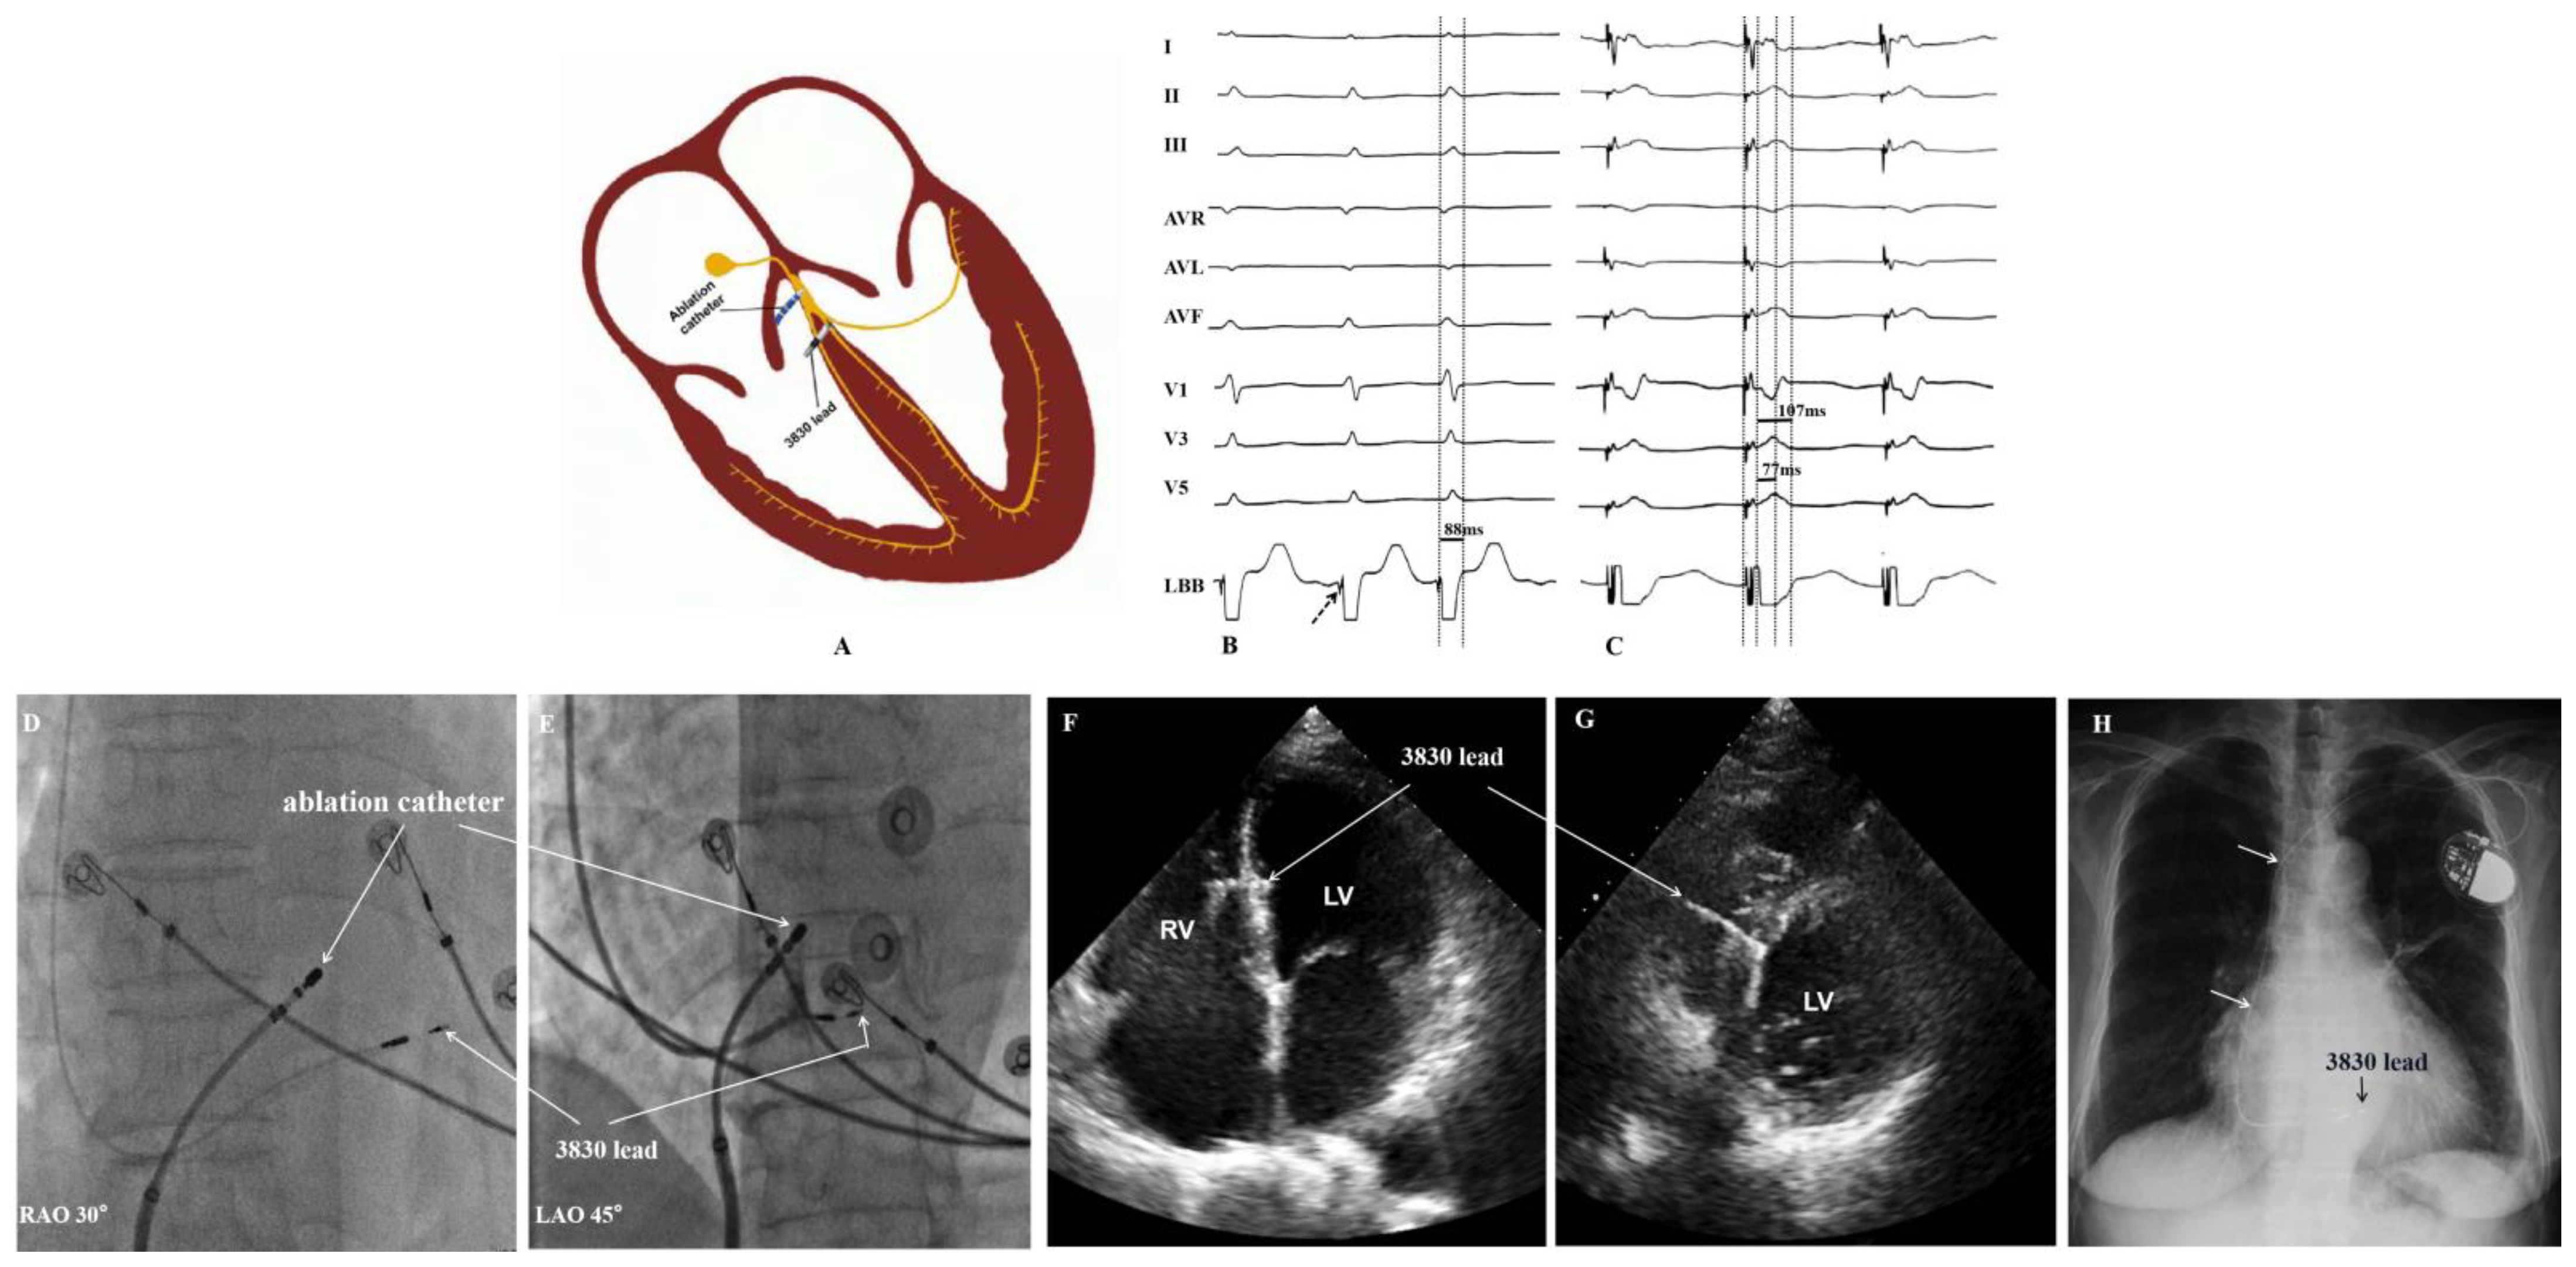

2.2.1. Left Bundle Branch Area Pacing

2.2.2. Atrioventricular Node Ablation